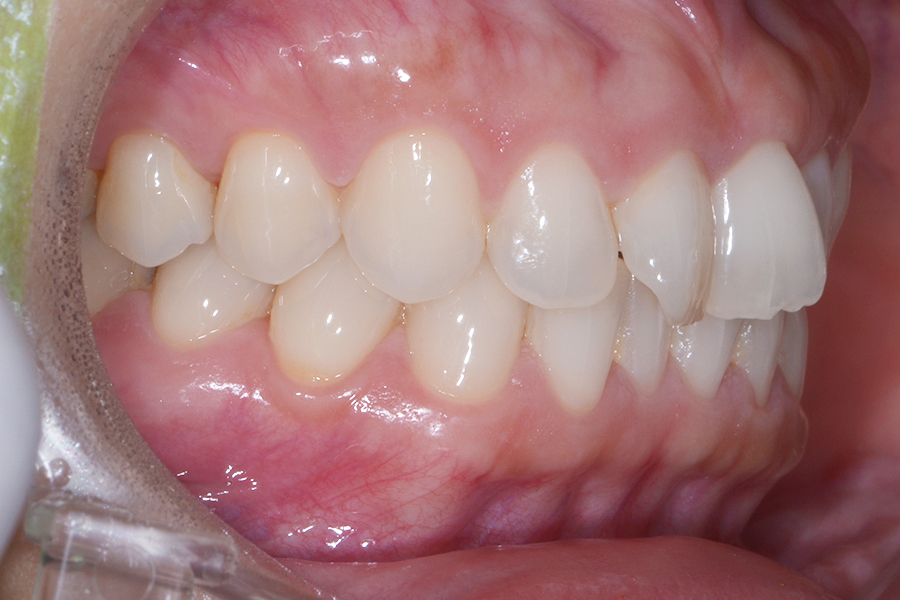

• 治療後

主訴 真ん中二本の捻じれた歯を治したい

期間 治療期間8か月

治療内容 上顎リンガル矯正(裏側矯正)